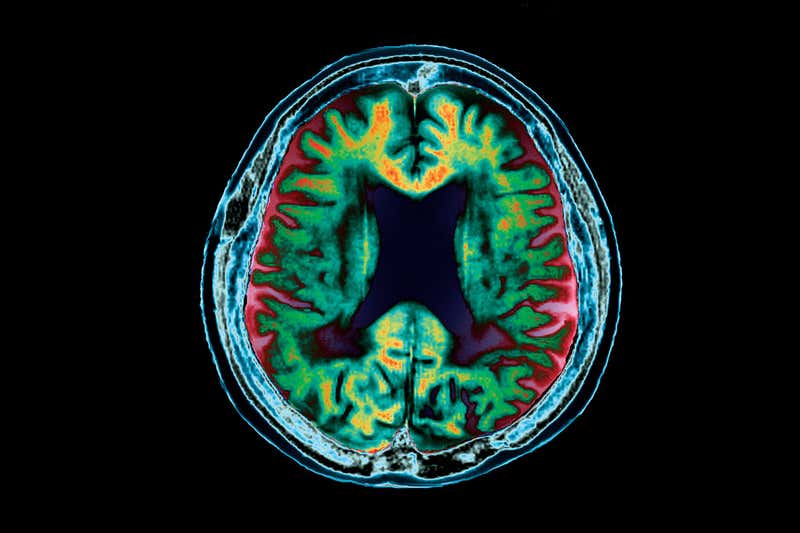

Sipas Organizatës Botërore të Shëndetësisë, sëmundja e Alzheimerit është forma më e zakonshme e demencës në mbarë botën, duke zënë 60-70% të të gjitha rasteve, ku numri i përgjithshëm i njerëzve që vuajnë nga kjo sëmundje arrin në 50 milionë në mbarë botën.

Sëmundja e Alzheimerit dhe llojet e tjera të demencës aktualisht nuk kanë shërim. Specialistët modernë të kujdesit shëndetësor vërejnë se problemet gjuhësore, çorientimi, ndryshimet e humorit, humbja e motivimit dhe shqetësimet e sjelljes janë të gjitha shenja të mundshme ndërsa gjendja përparon.